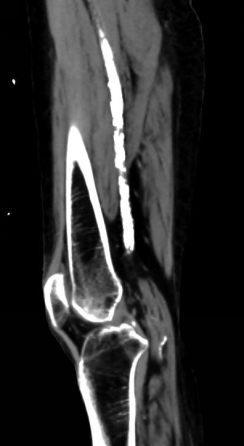

4. 开通胫前-足背动脉

5. 选择6*60mm Shockwave冲击波球囊处理股腘动脉

6. 股浅动脉下段置入6-150mm载药支架,于股浅动脉中上段置入6-220、 6-150mm载药球囊扩张

7. 术后造影血流恢复